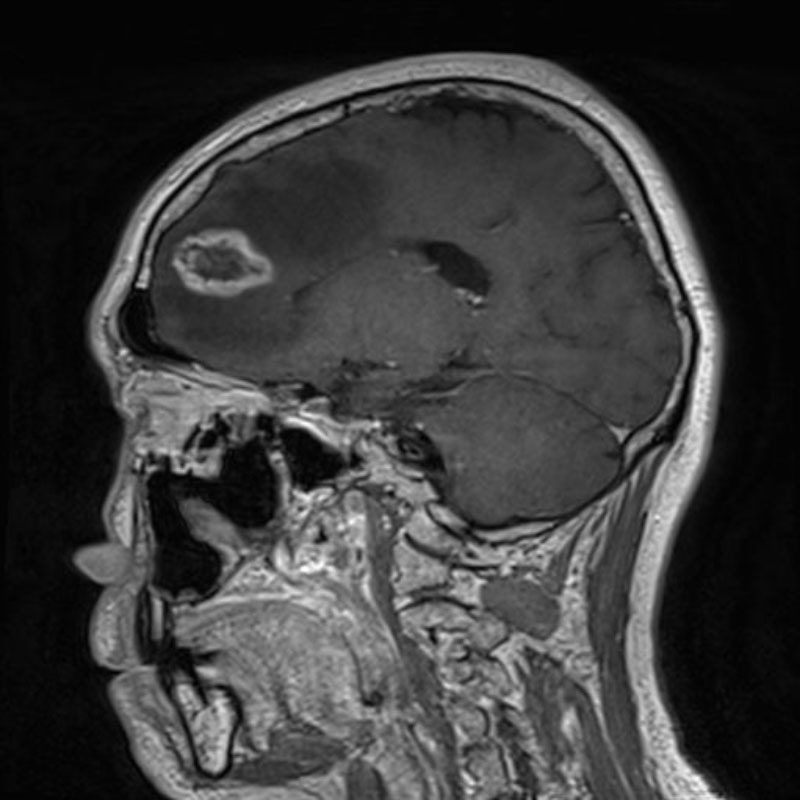

断層撮影

手術前1